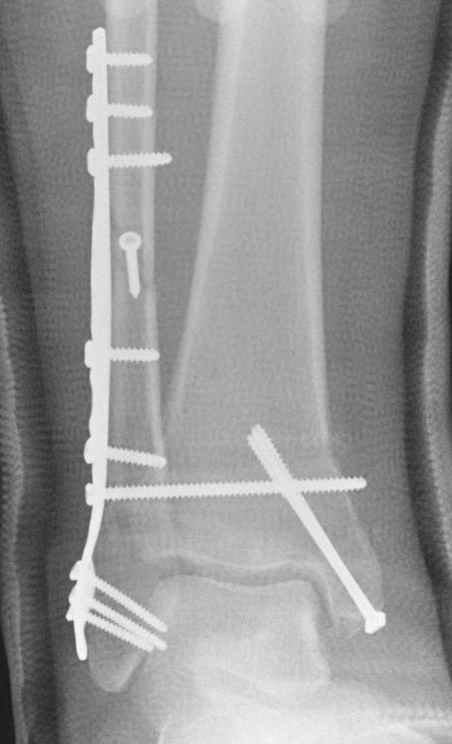

Недавний случай, больной 56 лет получил политравму в Англии, после переведен в США, где его успешно лечил местный ортопед, огромная статья в газете об успешной операции, своеобразный пиар, из-за того, что больной был американский пожарник на пенсии, и за его переезд было заплачено международным пожарным союзом, короче по другим показаниям перевели больного в наш университетский госпиталь.

После 5-6 недели после травмы сделана повторная операция, обошлись без удлинения малоберцовой.

Если до сих ничего не сделано, с артродезом сустава в данный момент я бы повременил, на выставленных январских снимках хорошо сохранившийся сустав, а в "мортиз" (трехчетвертной) и на боковых снимках не менее 5 мм укорочение малоберцовой кости. Косые переломы лучше фиксировать пластинами, как то мы разбирали случай, где было отмечено, что это закон "таранная кость всегда следует за малоберцовой".

В данном случаи я бы уговорил больного на реконструкцию, для этого после удаления шурупов, спереди очистить от рубцов синдесмоз, несросшуюся наружную лодыжку - остеотомия по линии перелома и компрессирующий (lagging technique) кортикальный шуруп 3.5 мм по поперечнику остеотомии. Следующий этап - восстановление длины малоберцовой за счет удлинения, сделать поперечную остеотомию где-то на уровне сантиметр выше вашего синдесмозного шурупа, наложить длинную пластинку, прикрепить пластину за дистальный конец двумя или тремя шурупами; сохраняя контакт пластины с костью, имеющимся

compression&tension device AO system (при отсутствии любой lamina spreader подойдет, создать дистанцию между пластиной и шурупом, проведенным проксимальнее пластины) толкая проксимальный отдел пластины, низвести пластину, мортиз рентгенограмма подскажет на сколько. Если заранее сделать предоперационный план (ренгенограмма другой стороны), тогда точно можно определить, на сколько вам необходимо сделать поперечную остеотомию малоберцовой кости, для закрытия создавшегося дефекта.

Убедившись, что желаемая длина восстановлена, окончательная фиксация пластины, при этом через пластину пару 3.5 мм шурупов на синдесмоз, предпочтительно в четыре кортекса и оставить на 3 мм длиннее, если под нагрузкой синдесмотический шуруп сломается, сломанный конец легче удалить с медиальной стороны.